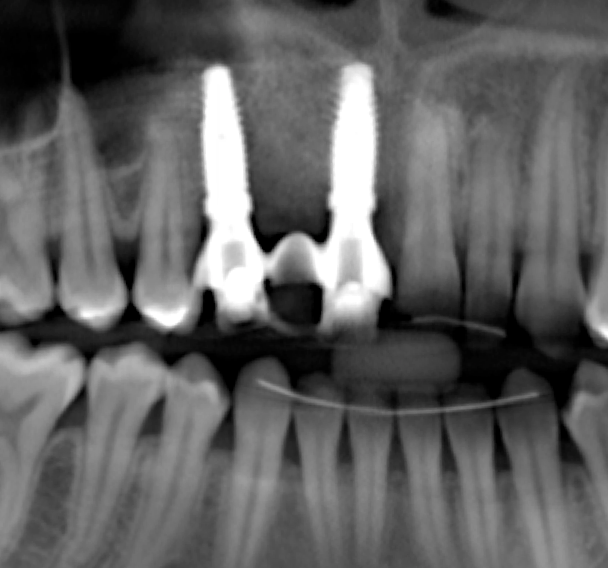

The bone graft underwent a 6-month maturation period to allow integration of the biomaterial. At this point, teeth Nos. 6 and 8 were atraumatically removed, and implants were immediately placed into the extraction sites without elevating a flap (Figure 19 through Figure 21). The gingival tissues exhibited a moderate degree of inflammation as a result of the difficult access for oral hygiene procedures under the post-orthodontic splint, which at the time had remained in place for 9 months. Implants featuring a tapered design were selected, and excellent primary stability was achieved (Figure 22 and Figure 23). Insertion torque values in excess of 45 Ncm were recorded for both implants, which allowed an immediate loading protocol.6,7,63,64

A screw-retained three-unit provisional prosthesis from teeth Nos. 6 through 8 was delivered during the same appointment (Figure 20). Additionally, direct composite occlusal overlays were bonded to the central fossae of the maxillary bicuspids and first molars to open the bite and disengage the maxillary anterior teeth, thus avoiding centric and excursive contacts during the osseointegration period.6-8,10,12

At the patient’s return visit 3 months after implant placement, the composite overlays were removed and the incisal edges of the provisional restoration were modified to approximate the length of the contralateral teeth. The patient reported no complaints, discomfort, or symptomatology throughout the osseointegration period. The implants were stable, and all discernable clinical parameters were within normal limits. The radiographic assessment revealed adequate bone-to-implant contact and osseous crest levels. Similarly, the peri-implant soft tissues displayed a healthy appearance and satisfactory gingival margin architecture (Figure 24 through Figure 27).

Fig 19. After extraction of teeth Nos. 6 and 8, implants were placed and a screw-retained immediate three-unit provisional was delivered.

Figure 19

Fig 20. After extraction of teeth Nos. 6 and 8, implants were placed and a screw-retained immediate three-unit provisional was delivered.

Figure 20

Fig 21. After extraction of teeth Nos. 6 and 8, implants were placed and a screw-retained immediate three-unit provisional was delivered.

Figure 21

Fig 22. The implants selected for teeth Nos. 6 (Fig 22) and 8 (Fig 23) featured a tapered design.

Figure 22

Figure 23

Fig 24. At 3 months post immediate implant placement and provisionalization, complete regeneration of the defect and adequate osseous crest

levels and bone-to-implant contact were evident radiographically.

Figure 24